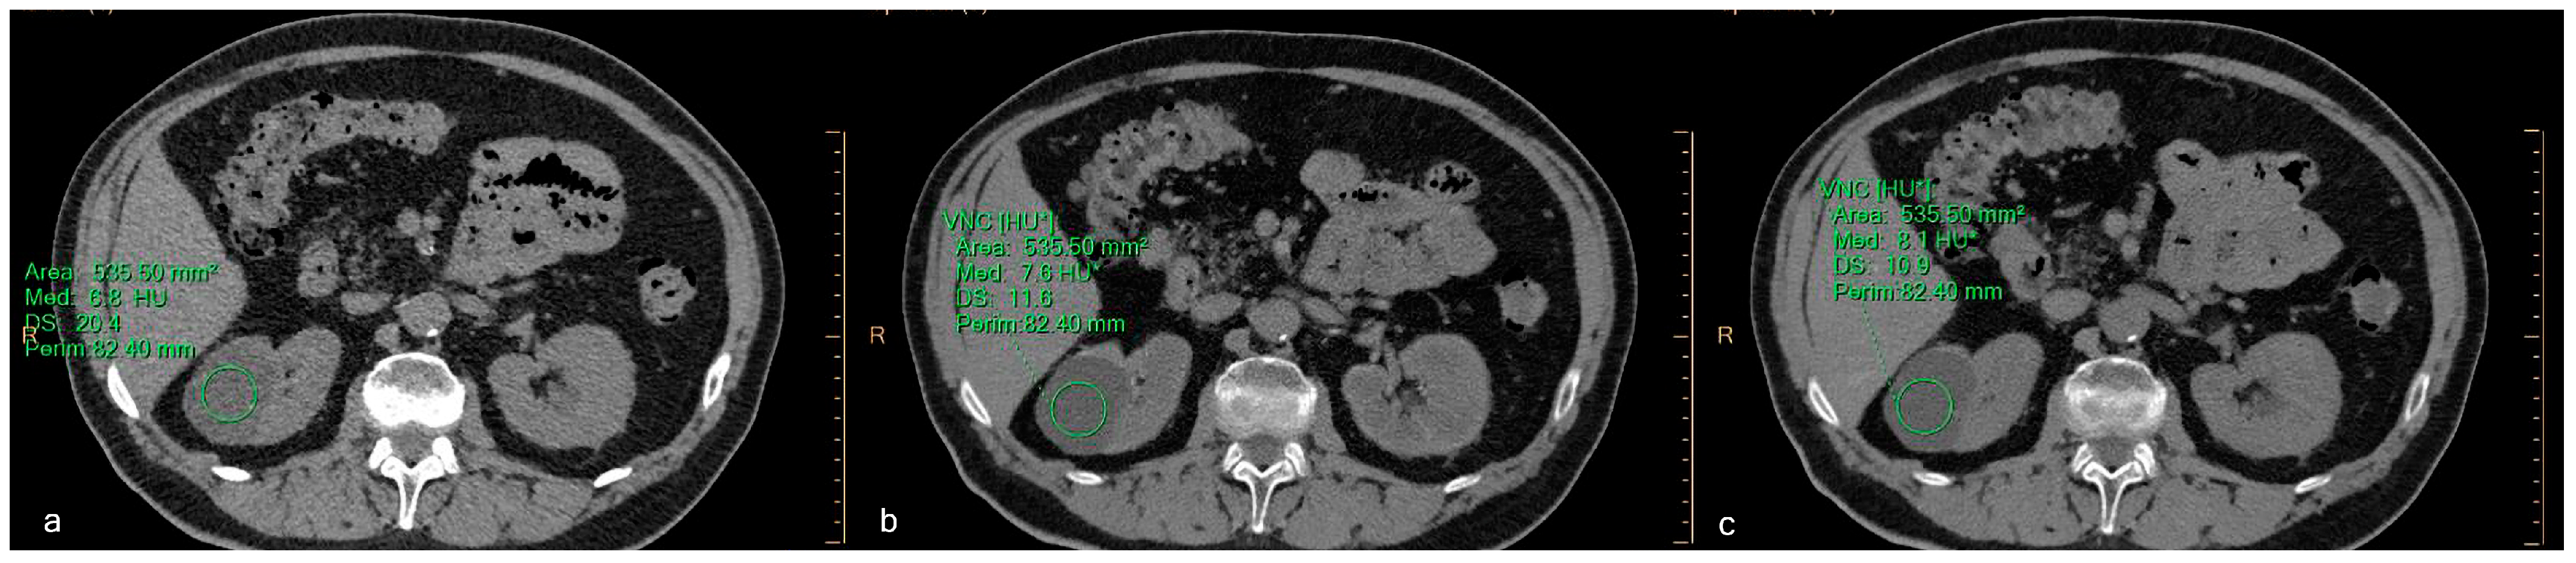

Virtual Non-Contrast Spectral CT in Renal Masses: Is It Time to Discard Conventional Unenhanced Phase?

3. Results

3.2. Quantitative Assessment